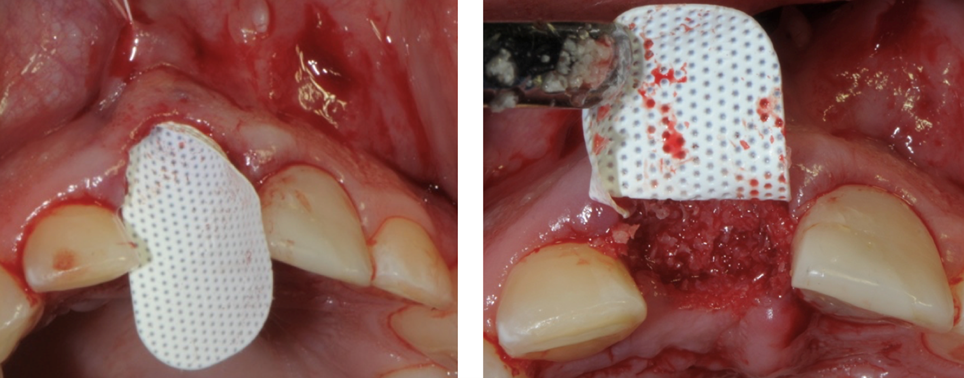

Evidenza clinica della mancanza di parete vestibolare

Inserimento della membrana in dPTFE Cytoplast TXT 1224 tramite sutura e posizionamento di sostituto osso suino ad alta porosità Zcore™.